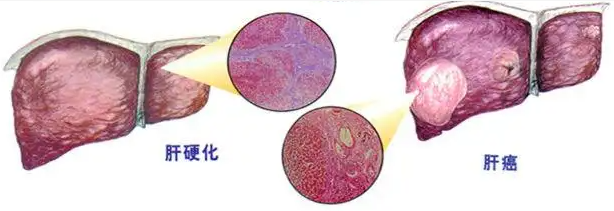

答:肝硬化,实际上我们在区分的时候,它就是有结节的,一般是看纤维化的程度,纤维化程度重的地方,会形成纤维结缔组织的集聚,形成结节。这个结节会有变化,它会增大,会融合,会癌变。

有的时候,要区别肝硬化结节和肝癌,还是挺难的,为什么呢?因为它可能是一个量变的过程到质变的过程,我们要想早期区别,是肝硬化的结节,还是一个早期的肝癌,确确实实还是有一定难度,不过我们现在也有一些办法,是可以做出一些早期判断的。

那么肝硬化结节与肝癌最主要的区别点在什么地方?

第三个,我们还可以通过一些影像学的造影技术,看看这个结节里面,是静脉供血还是动脉供血;